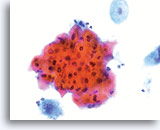

The ThinPrep Pap Test® minimizes the troublesome artifacts inherent in smear and spray fixation. This allows for

the nucleus to be adequately visualized facilitating a more definitive diagnosis. The epithelial cells that are generally incorporated in the ASC category are the mature squamous and squamous metaplastic cells exhibiting changes that are minimal and fall short of a diagnosis of LSIL or HSIL. The nuclei are slightly enlarged and this enlargement is compared to the normal entity of the same cell type. The nuclei may show slight nuclear membrane irregularities but are more often smooth. When dealing with the metaplastic component, one needs to make sure that the irregularities aren’t due to a vacuole(s) pushing the nucleus into the aberrant shape. The chromatin pattern is finely granular and evenly distributed. Chromocenters or nucleoli are generally inconspicuous or absent unless a reactive process is occurring in conjunction with the atypia at which point the differential diagnosis of reactive needs to be considered depending upon the presence or lack of the other criteria.

With either conventional or ThinPrep® slides, an ASC interpretation may arise from any of several different cellular changes, including but not limited to, squamous atypia, atypical squamous metaplasia, and atypical parakeratosis. The criteria for ASC on the ThinPrep Pap Test are as follows:

The images that follow are ThinPrep® Pap Test specimens that reasonably could be interpreted as reactive changes,

ASC-US, and LSIL.